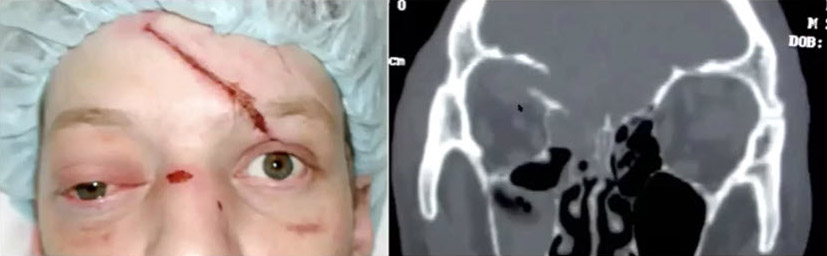

Roof fractures are often blow-in type fractures in which the bone fragments push down into the orbit. The patient will present with proptosis—the eye will be down and out—they might have double vision and sometimes significant pressure on their globe, so we often want our ophthalmology colleagues involved as well.

Roof fractures can be significant issues, so when you're in the emergency room you want to check if the patient has double vision, if they can move their eye, if they have ptosis, if they have mydriasis. These are important things to rule out.

Now, let's look at orbital floor fractures. These fractures tend to occur in slightly older children when the maxillary sinus develops, and it’s where we see the most serious problem in the eye. The Trapdoor fracture—or white-eye blowout as we call it—is a pediatric problem, and it’s extremely rare in adults. The patient will often present with no bruising or swelling. They look fine except they may have nausea and vomiting. However, they will have pain if they move their eye, and sometimes they don’t want to open their eyes because it hurts, so they’re squinting. This unique pediatric injury involves the squeezing of the inferior rectus muscle in the fracture site. That muscle, if not released, will undergo necrosis and the patient will have diplopia for the rest of their life, so this is an emergency. They might present squinting, or they cannot look up when asked—which is a big concern. The key is to take them emergently to the operating room in order to release the trapdoor, enlarge the fracture and free up the inferior rectus muscle.